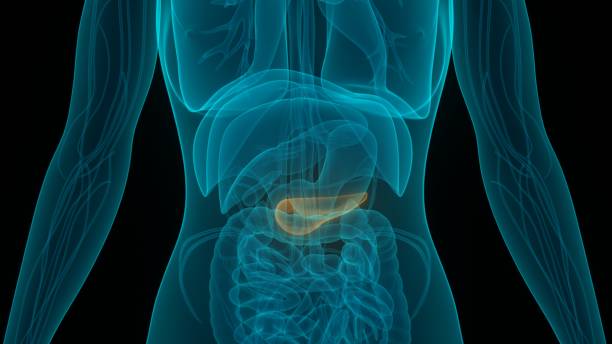

췌장암 초기증상 알아보기

금일 알아보고자 하는 췌장암의 경우 10가지 암 중에 8위에 차지하여 발생비율은 높지 않았지만 5년암상대생존율과 10년 암상대생존율 역시 하위권에 위치하여 완치가 쉽지 않음이 다시금 확인되었습니다. 따라서 이번 시간에는 어떤 암보다 빠른 대처가 필요한 췌장암 초기증상에 대해 정리해보고 자세히 알아보겠습니다.